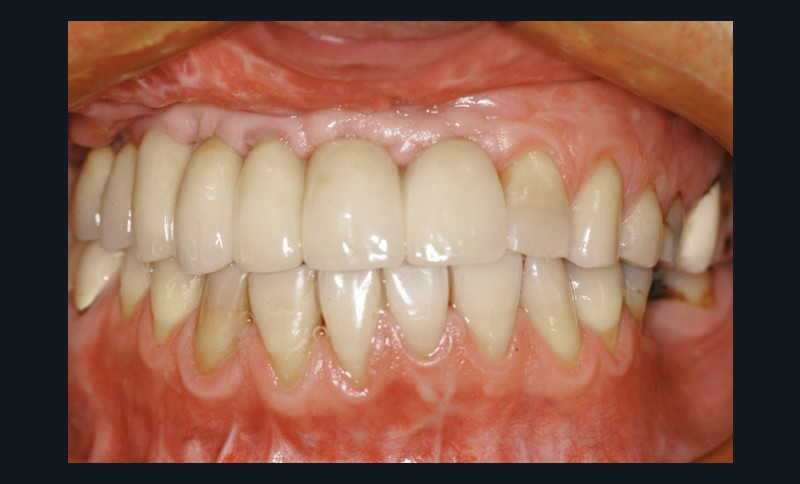

Car ce sont bien des situations cliniques exceptionnelles que ce conférencier a prises en charge, non pas seul, mais en constituant une équipe multidisciplinaire plus à même de relever les défis fonctionnels, structurels, biologiques et esthétiques en présence. Après avoir passé en revue les composants essentiels à l’obtention d’un sourire équilibré, Nadim Aboujaoude a évoqué les travers des traitements dits esthétiques mais conduits sans planification globale et qui engendrent des résultats disgracieux. Depuis de nombreuses années, l’engouement pour les solutions esthétiques ne faiblit pas. La divulgation médiatique des progrès technologiques et chirurgicaux réels encourage une part croissante de la population à recourir à des procédures souvent fiables, mais parfois portées au-delà des limites raisonnables. Ainsi, des traitements de médecine esthétique inadaptés engendrent un effet de « ligne de sourire basse » accompagné d’une exposition exagérée des incisives mandibulaires.

La demande de correction de cette anomalie esthétique incite les patientes à rechercher une compensation prothétique (à travers un abaissement des bords incisifs maxillaires visant à rendre sa visibilité au groupe incisivo-canin maxillaire) qui concoure à recomposer les rapports des étages de la face (en minorant l’étage inférieur et majorant l’étage moyen). La reprise de ces cas cliniques se révèle particulièrement délicate et repose sur une analyse rigoureuse des clefs esthétiques de l’harmonie du sourire et de son rayonnement au sein du visage.

Concernant le versant orthodontique des traitements multidisciplinaires, Nadim Aboujaoude intègre cette thérapeutique moins invasive à ses traitements multidisciplinaires sans rechercher une occlusion de classe 1 mais en privilégiant l’obtention de situations facilitant les solutions prothétiques, parodontales ou implantaires : en redistribuant et optimisant les espaces prothétiques, en corrigeant les malpositions dentaires, en remplaçant les dents compromises par les dents adjacentes, en harmonisant les contours gingivaux, en optimisant l’inclinaison des racines dentaires et en créant des volumes osseux favorables à la mise en place d’implants. À l’issue d’une présentation riche en prise en charge thérapeutique de cas complexes, le conférencier a clairement démontré que toute solution thérapeutique ne peut se concevoir et s’établir que dans une logique multidisciplinaire axée sur la concertation.